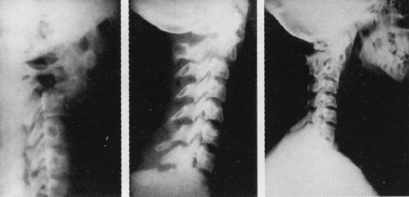

неврологическая симптоматика (геми-, тетрапарезы). Галоаппарат монтировался

из деталей аппарата Илизарова. Чаще аппарат накладывался под наркозом, хотя

возможно его наложение и под местной анестезией. После наложения кольца больному

накладывался гипсовый корсет типа "майки", в корсет вгипсовывались

4 телескопические штанги (2 спереди и 2 сзади), которые через шарнир фиксировались

к кольцу (рис. 1). Тракция проводилась постепенно в среднем на 0,5-1

Для иллюстрации приводим два клинических наблюдения.

Больная П.,

23 лет. Попала в автоаварию. Была доставлена машиной скорой помощи в Центральную

районную больницу, где диагностирован ушиб головного мозга, во время выполнения

первичной хирургической обработки раны на голове у больной произошли остановка

дыхания и падение артериального давления. После проведения реанимационных мероприятий

были проведены рентгенограммы шейного отдела позвоночника, на которых диагностирован

перелом дужек С2 и спондилоптоз С2 относительно С3 (рис. 2). Больной

было наложено вытяжение шейного отдела позвоночника за скуловые дуги и после

стабилизации состояния больная была переведена в ЦИТО. При поступлении у больной

не было выявлено спинальной симптоматики, за исключением оживления сухожильных

рефлексов. На 2-е сутки после поступления больной был наложен галоаппарат, дана

тракция. В аппарате достигнуто вправление позвонков.

Через 3 мес аппарат снят. Больная 4 нед носила головодержатель из вспененного

полиэтилена. На контрольных рентгенограммах - достигнуто сращение. Через 4 года

на рентгенограмме шейного отдела нестабильности нет (рис. 2), имеется

спонтанный передний спондилодез. Больная активна, работает, болевого синдрома

нет.

Рис. 2. Травматический cпондилолистез С2, вправление

в галоаппарате, спонтанный передний спондилодез. |